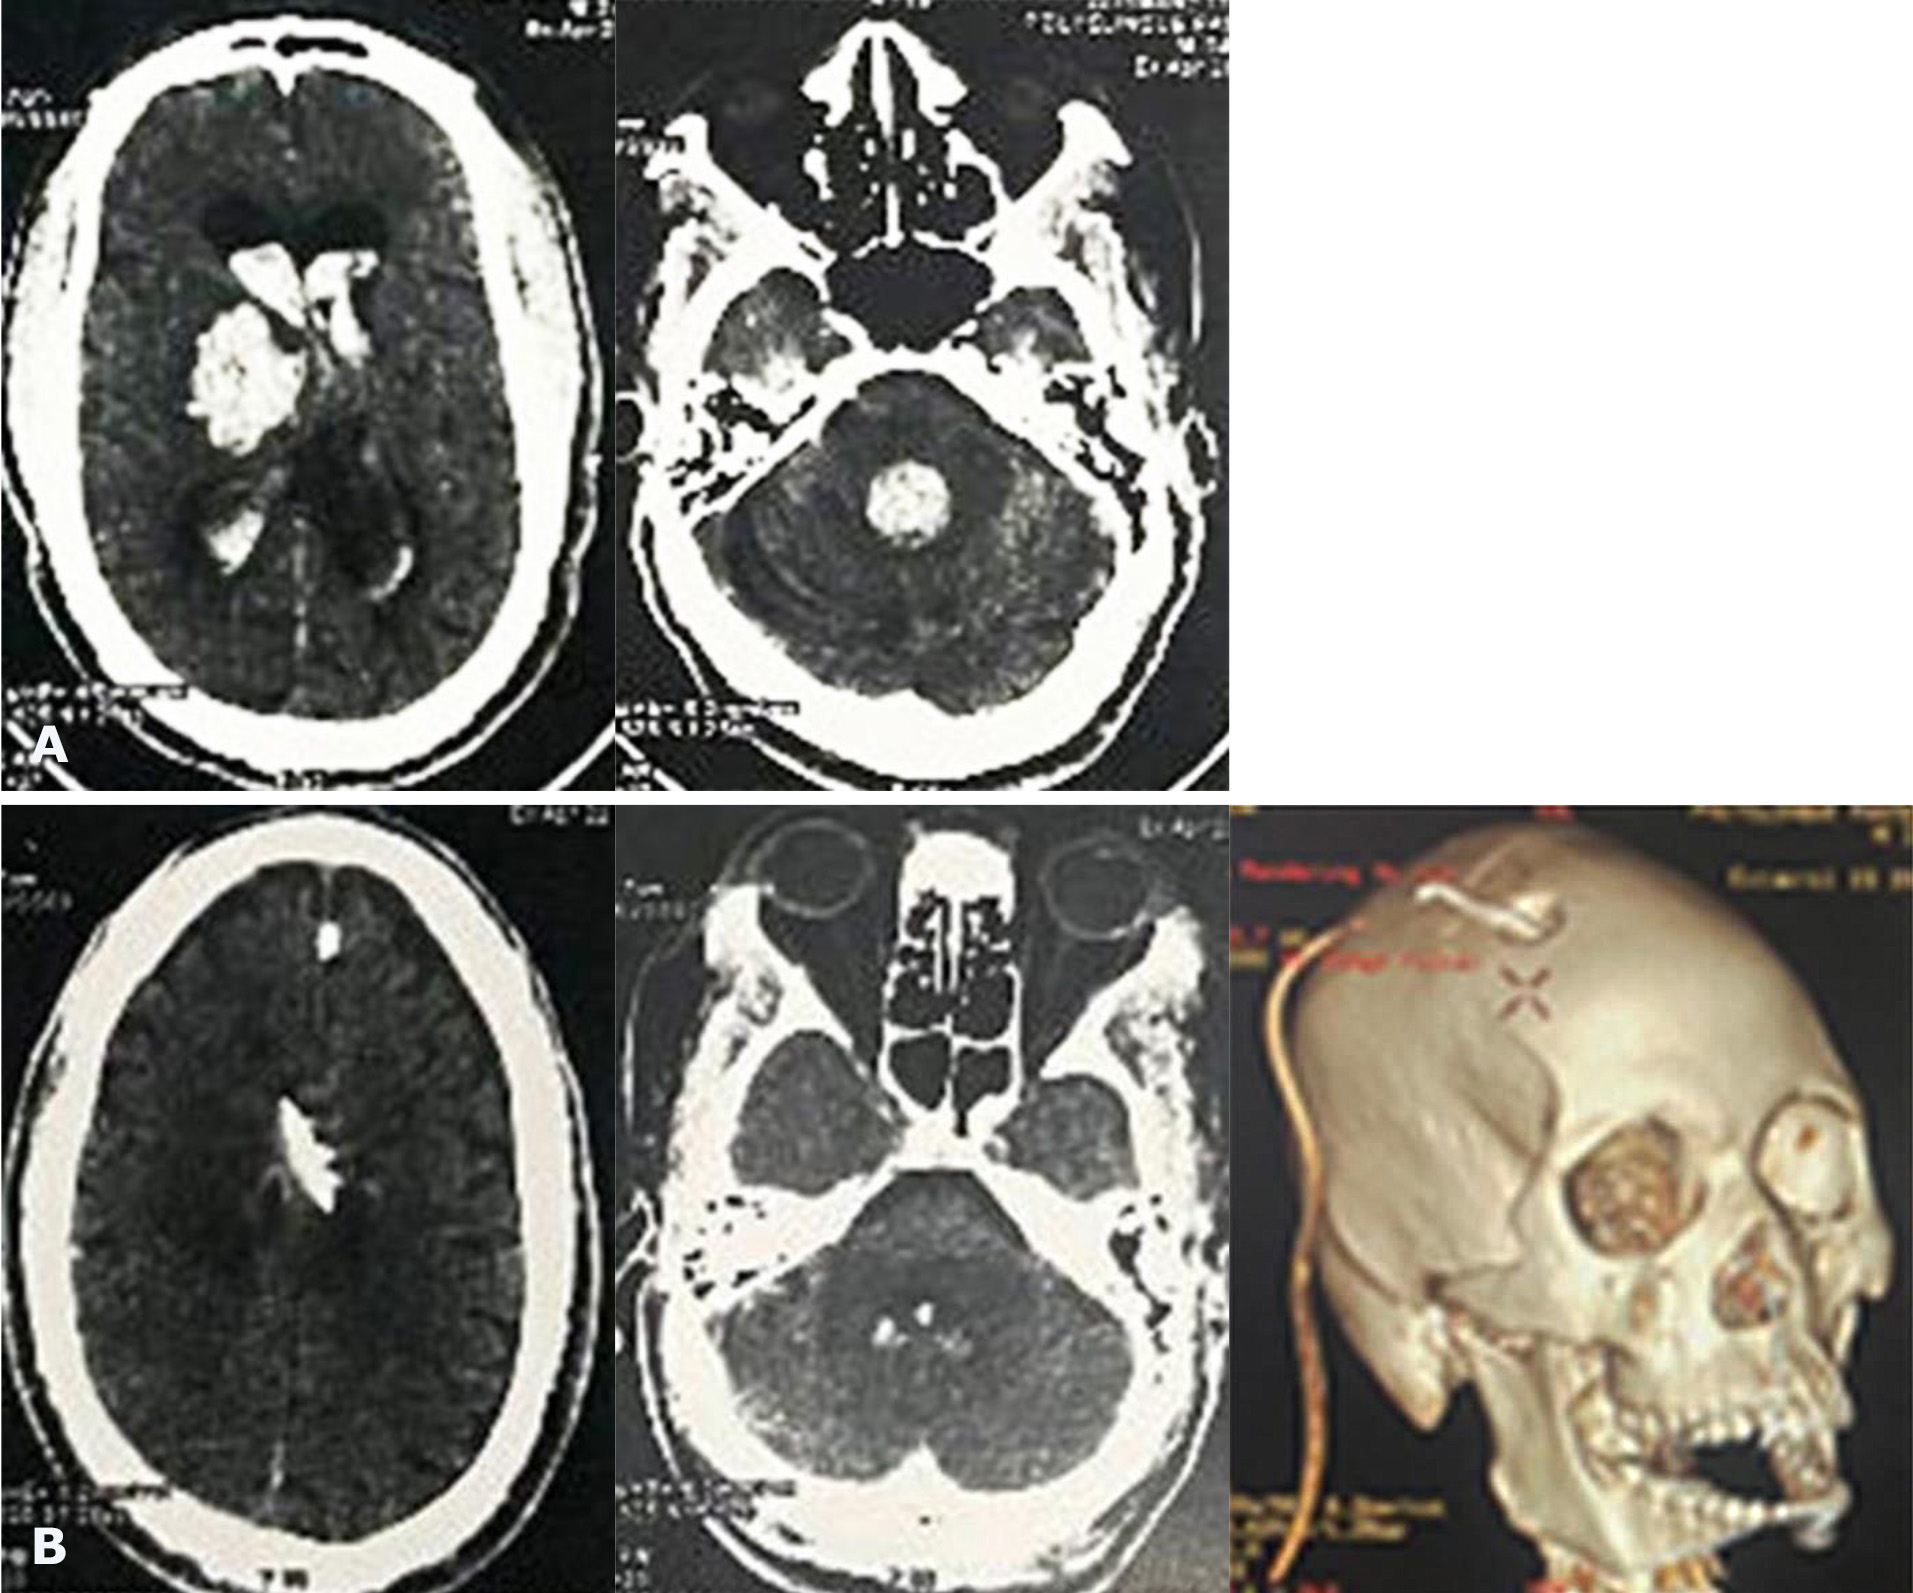

During the study period, a total of 63 patients were admitted for spontaneous ICH and IVH was associated in 24 (38.1%) patients. Among them, EVDs were placed in 17 patients. The mean age was 49 years with range of 27 to 66 years. There were 11 males and 6 females. The main risk factors of stroke were hypertension in 13 patients and diabetes in 7 patients. The initial GCS was between 5 and 8. Unilateral pupillary dilatation was found in 8 patients (Table 1). EVD was placed in frontal horn in the lateral ventricle in all cases (Fig. 1, 2) and continuous CSF drainage was indicated leading to ventricle size and blood clot removal (Fig. 2, 3). The duration of EVD was 1 to 8 days. Four (23.5%) patients experienced infection as a complication. The short-term mortality rate was 70.5 % at 30 days including 8 males and 4 females with a mean age of 53 years. The functional outcomes were poor in 4 patients with mRS sore of 4 and 5 (Table 2). The independent predictor factors for 30-day mortality (Table 3) were poor GCS (p=0.319), mydriasis (p=0.245) and poor Graeb score (p=0.004).

Fig. 2. Preoperative CT scan showing ICH with IVH (A), and postoperative CT scan showing intraventricular catheter tip in the ventricle as well as the decrease of ventricle size and hematoma (B)

Fig. 3. Preoperative CT scan showing IVH (A) and postoperative CT scan showing the complete evacuation of IVH after EVD (B) with the burr hole in 3D (C)